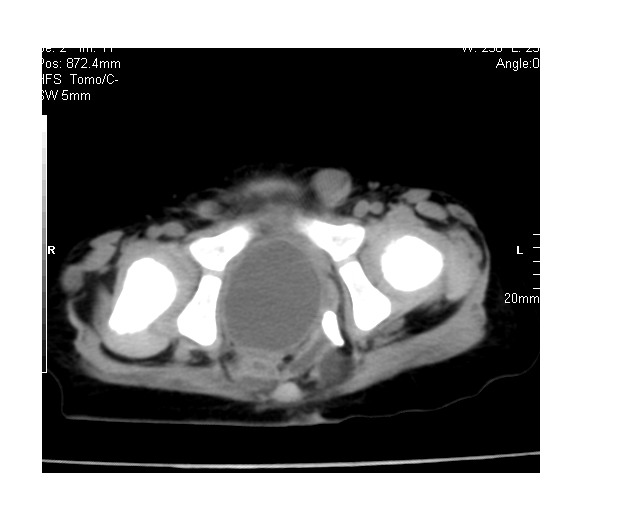

以下是引用lkc8963在2008-3-16 12:49:00的发言:[br]盆底巨大混杂密度肿块,富含多种组织成分包括脂肪/液体/软组织/钙化,边界清楚,向前压迫肠管及膀胱,向后突入骶尾部皮下脂肪层,首先考虑畸胎瘤,诊断时需要与脊柱裂/囊性淋巴管瘤等区别。